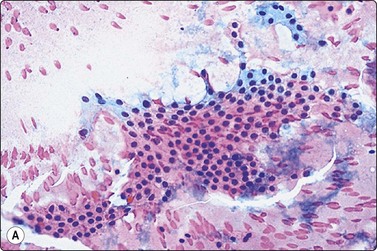

image image image

Fig. 6.28 Poorly differentiated carcinoma

(A,B) Smears showing syncytial clusters of crowded small cells with hyperchromatic nuclei (A, MGG, HP; B, Pap, HP); (C) Tissue section, same case. (H&E, IP).

Until recently, thyroid carcinoma with a poorly differentiated insular pattern was considered to be a distinct entity, a thyroglobulin-producing neoplasm, intermediate in aggressiveness between well-differentiated and anaplastic thyroid carcinoma. Reports have appeared documenting cytological features in insular carcinomas such as high cellularity, dispersed and loosely aggregated cells, solid, cohesive trabecular or papillaroid structures, intact insulae, fragile, ill-defined, granular cytoplasm, oval, hyperchromatic nuclei, occasional INCIs and/or grooves.151-155 However, as insular pattern is often admixed with trabecular and solid growth patterns, the more suitable term ‘primordial carcinoma’ was suggested for this entity.156

The current concept of pure poorly differentiated thyroid carcinoma, as per the Turin proposal156 is one that shows a histologically mixed solid/trabecular/insular architecture, absence of conventional nuclear features of PC and the presence of one of the following three features: cells with convoluted (raisin-like) nuclei, a mitotic index of ≥3 mitoses/10 high-power fields and tumor necrosis. Most tumors are immunohistochemically positive for thyroglobulin and thyroid transcription factor 1, and a subset is also positive for p53.157 Ras mutations are common.

Smears in poorly differentiated thyroid carcinomas are hypercellular with single cells as well as cells in solid, trabecular and insular patterns. There is marked crowding of cells and tumor cells show high nuclear cytoplasmic ratios (Fig. 6.28).158